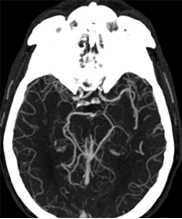

A CT angiogram is ordered for the patient. Results are shown in Figure 3.

Figure 3. The patient’s CT angiography scan showing (A) intracranial axial view and (B) right carotid sagittal view.

The patient’s CT angiography scan shows she suffered abrupt cessation of blood flow due to occlusion of the right internal carotid artery terminus and right middle cerebral artery but maintained some distal cerebral collateral flow (Figure 4A). The likely etiology of the patient’s occlusion is symptomatic carotid atheroemboli from severely stenotic proximal right cervical internal carotid artery (Figure 4B), and recanalization should be considered for secondary stroke prevention moving forward. (Further discussion of this is beyond the scope of this case.)

A.

B.

Figure 4. Patient’s CT angiography scan (from Figure 3). Figure 4A shows abrupt cessation of blood flow caused by the occlusion of the right internal carotid artery terminus and right middle cerebral artery (solid yellow arrow) while maintaining some distal cerebral collateral flow (white arrows). On Figure 4B, the open yellow arrow points to the symptomatic carotid atheroemboli from severely stenotic proximal right cervical internal carotid artery.